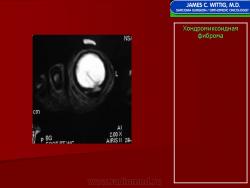

Хондромиксоидная фиброма

Хондромиксоидная фиброма

Хондромиксоидная фиброма

Хондромиксоидная фиброма

Хондромиксоидная фиброма

Хондромиксоидная фиброма

Микроскопическая картина хондромиксоидной фибромы представляет сочетание звездчатых или вытянутых клеток в миксоидной или хондроидной строме. В ряде случаев преобладает дольчатая структура с малым количеством клеток в центральных отделах опухолевых долек и гиперклеточными периферическими отделами.

Иммуногистохимия. Клетки хондромиксоидной фибромы положительно реагируют с белком S-100. По периферии долек отмечается иммунореактивность клеток с гладкомышечным актином и CD34. Встречаются клеточные отростки, волнистость клеточной мембраны, цитоплазматические фибриллы и наличие гликогена, а также типичные хондроциты, миофибробласты и промежуточные формы.